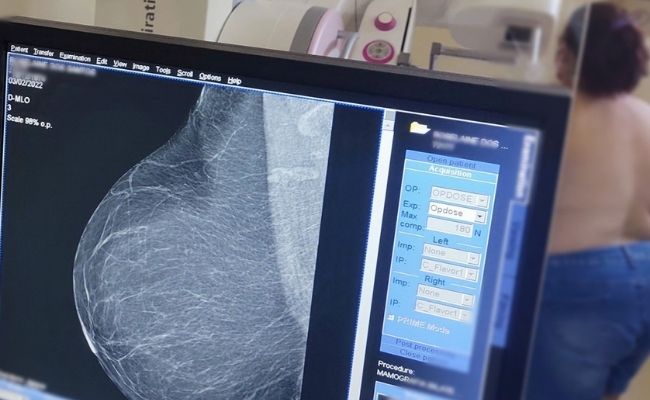

Mamografias serão agendadas diretamente nas unidades de saúde de Novo Hamburgo

Alteração quer facilitar acesso ao exame de prevenção ao câncer de mama

A partir desta terça-feira (1.º/07), as usuárias da rede municipal de saúde de Novo Hamburgo passarão a contar com uma novidade. As mulheres que necessitarem realizar mamografia sairão da unidade de saúde com o exame agendado.

O Município realiza cerca de 900 mamografias ao mês. O Ministério da Saúde e o Instituto Nacional do Câncer (Inca) recomendam que o exame seja feito a cada dois anos por todas as mulheres entre 50 e 69 anos.

A mamografia é um exame não invasivo e que deve ser feito, inclusive, por quem tem próteses mamárias. Quanto mais cedo o tumor for identificado, maiores são as chances de cura. Para câncer de mama, os casos identificados no início trazem um índice de cura que pode chegar a 98%.